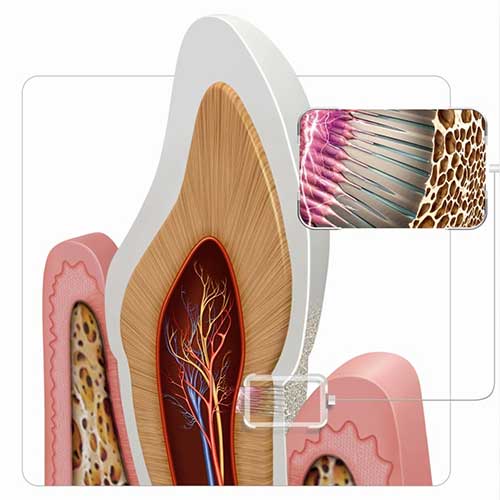

¿Qué es la sensibilidad dental?

Es el dolor o molestia que se produce debido a un desgaste de la superficie dental o retracción del tejido gingival.

Hipersensibilidad dental en el consultorio y en casa

La hipersensibilidad dental es un padecimiento muy frecuente, por lo que revisar a sus pacientes y brindarles soluciones para controlarla son habilidades esenciales para cualquier profesional de la salud dental.

Cómo evaluar la hipersensibilidad de la dentina

Hay un gran número de pacientes que no hablan sobre su hipersensibilidad de la dentina. A continuación, hablaremos de cómo las y los dentistas pueden ayudar a empezar la conversación para brindar cuidados holísticos y efectivos.

Hipersensibilidad de la dentina: ¿qué es lo que callan nuestros pacientes?

A menudo hay pacientes que no hablan con sus dentistas acerca de sus síntomas de hipersensibilidad de la dentina. ¿Por qué no lo mencionan y cómo podemos ayudarles?

Hipersensibilidad de la dentina: ¿por qué afecta a algunas personas y a otras no?

Descubra por qué algunas personas tienen una mayor probabilidad que otras de sufrir de hipersensibilidad de la dentina y cómo las y los estudiantes de odontología pueden reconocerla, diagnosticarla y tratarla.

La importancia de la prevención y el control de la hipersensibilidad de la dentina en pacientes con periodontitis

Manejar y prevenir el dolor causado por la hipersensibilidad de la dentina en pacientes con periodontitis es de suma importancia, y algunas de las soluciones son muy simples.

La tecnología pro-arginina: Una solución de beneficios múltiples para sus pacientes con dientes sensibles

Mejore la salud bucal y la calidad de vida de sus pacientes con una pasta dental especial para la sensibilidad dental, una solución altamente efectiva y basada en evidencias para tratar la hipersensibilidad de la dentina.

Pasta dental para la sensibilidad: Por qué la tecnología importa

A la hora de hablar de remedios para la hipersensibilidad de la dentina, la tecnología importa. En este artículo hablaremos de por qué las y los estudiantes de odontología pueden recomendar la tecnología pro-arginina con confianza.